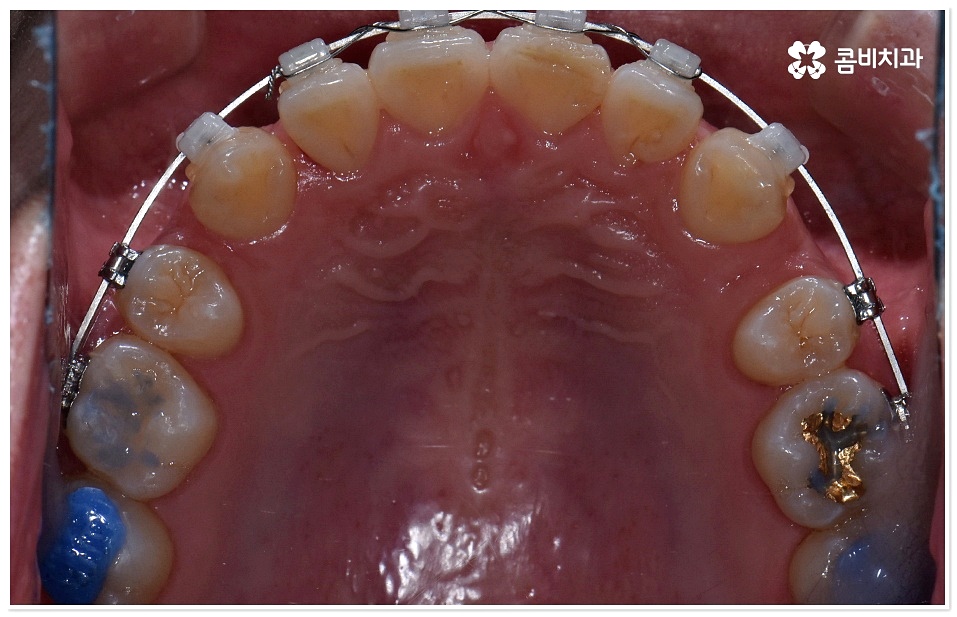

심리적, 심미적으로 좋지 않은 영향을 줄 뿐 아니라 치아의 기본적인 저작 역할 및 정확한 발음을 하는데도 기능적으로 문제를 일으킬 수 있기 때문에 아마도 많은 분들이 치아 배열과 교합을 정상적인 상태로 바꾸고자 한번쯤 교정 치료에 대해서 생각해 보셨을 거예요. 특히 부정교합이나 불규칙한 치열은 턱관절에도 좋지 않은 영향을 줄 수 있고 고르지 못한 치아 사이 사이에 음식물 찌꺼기가 끼게 되면 제거가 어려워 충치, 잇몸 염증 등 구강 질환의 원인이 될 수도 있기 때문에 덧니치아교정 등의 치료로 개선해 주실 필요가 있습니다.

교정 치료란 특수한 장치를 이용해 치아를 원하는 방향으로 이동시켜 치아 배열과 교합을 올바르게 개선해 주는 과정으로 각자의 구강 구조가 다 다르기 때문에 정밀 검사를 통해 환자분들 각각의 치아 모양과 각도, 위치, 교합 뿐 아니라 잇몸 건강 상태 및 상악과 하악의 관계와 같은 구강 내 상황과 함께 입술, 전체 안모 등 대칭과 균형의 측면에서 모든 부분을 다각적이고 입체적으로 분석한 후 세밀한 맞춤 계획을 수립하는 것이 중요할 수 있는데요.

그러므로 3D CT와 같은 정밀 검진 장비와 3D 모르페우스와 같은 시스템을 갖추고 다양한 경험과 노하우를 바탕으로 정확한 진단 및 섬세한 플랜을 세울 수 있는 치과를 잘 알아보고 덧니치아교정 치료를 진행하실 필요가 있어요.